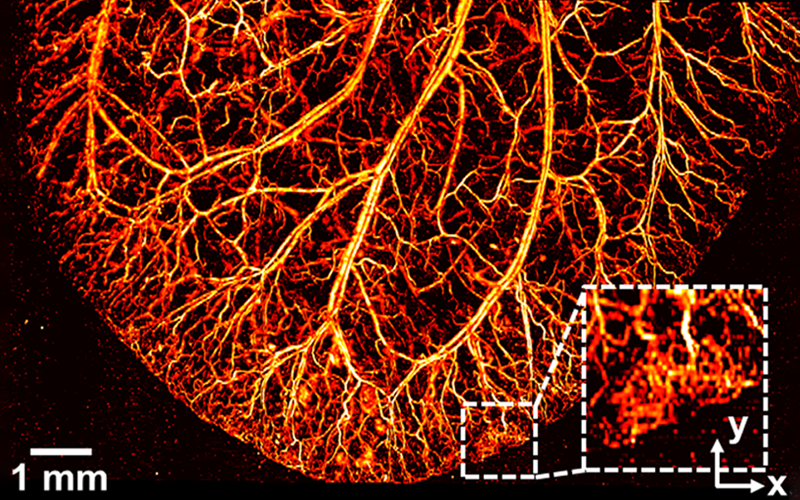

Mouse ear

J. Kim, et al., Light Science & Applications, Vol. 8, 103 (2019)